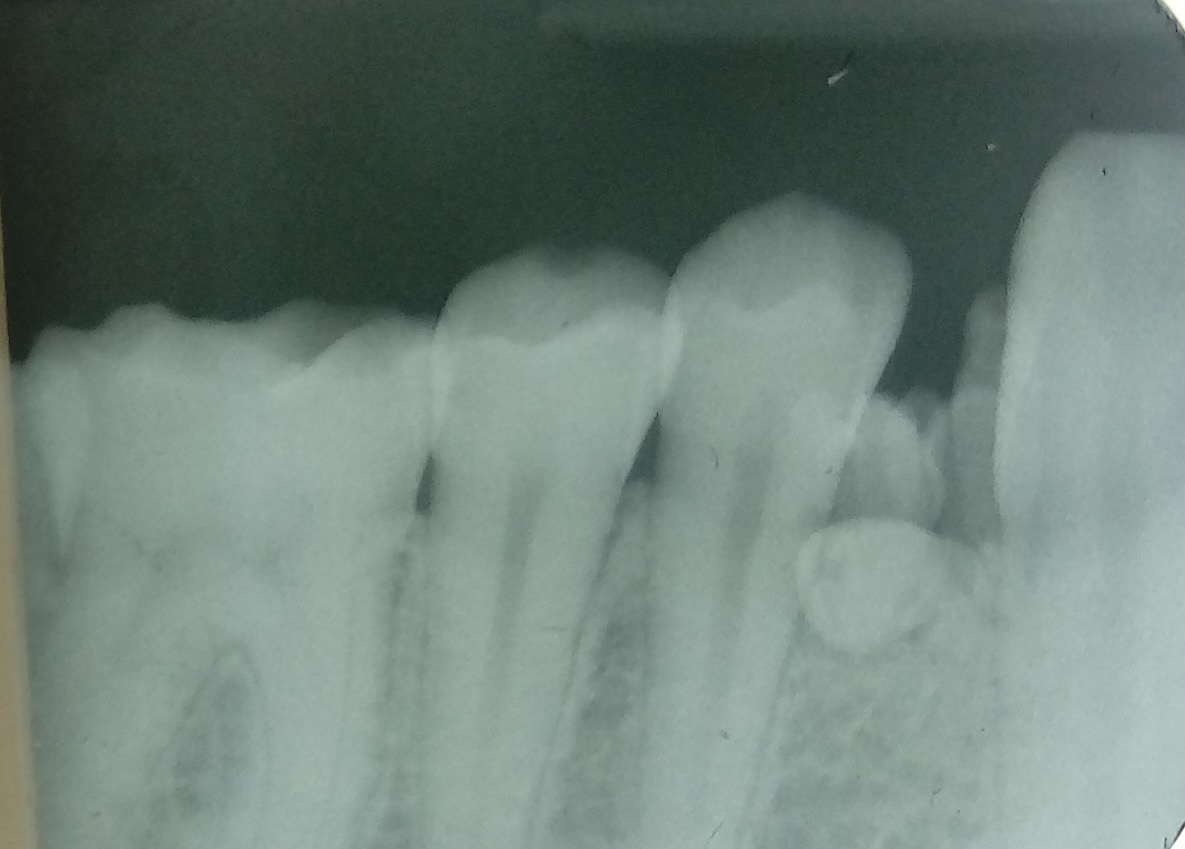

Recently, there has been improvement in X-ray diagnostic imaging methods, especially with regard to CBCT, which certainly facilitates arriving at diagnosis as early as at the stage of radiological examination. Jayam et al. describe a case of an 11-year-old girl with a radiological picture (panoramic radiography, a tooth X-ray and a maxillary occlusal radiograph) description of impacted tooth 11 with an additional cusp and an extensive dentigerous cyst.2 In the course of marsupialization, the dentigerous cyst was found to have no contact with tooth 11, while it contacted the adjacent additional cusp. On histopathological examination, OCp was diagnosed with a cyst. According to some authors, X-ray images – panoramic radiographs and targeted dental X-rays – may not accurately reveal the pattern of the lesion, which is why cross-sectional CBCT is recommended in the case of doubts or for more accurately determining the location.2 In the case of 2 of our patients, it was not until a CBCT was performed that the adequate diagnosis was reached, and it was later confirmed during the procedure and histopathological examination. The first patient was a 9-year-old girl referred to an orthodontist in our clinic due to impacted tooth 21 for the exposure of the tooth and the application of a bracket to the crown of tooth 21. The patient had with her a current panoramic radiograph with visible impacted tooth 21, showing a small non-distinctive radiopacity in the tooth crown, which could be consistent with an additional cusp. An X-ray of tooth 21 was performed at our clinic, revealing a non-distinctive area of radiopacity next to the crown of tooth 21 (Figure 7). The patient was referred for cross-sectional CBCT. After verification, OCp was diagnosed and removed with its capsule, and an orthodontic bracket was attached to tooth 21 in local anesthesia (Figure 8). Histopathological examination confirmed the preliminary diagnosis of OCp. The other patient was a 5-year-old girl who was admitted to our clinic with a missing deciduous tooth 65. The patient had a current panoramic radiograph with her, revealing an impacted tooth (most probably tooth 65) with a non-distinctive area of radiopacity (Figure 9). Cross-sectional CBCT was recommended. In the X-ray image, the preliminary diagnosis suggested OCp with the impacted deciduous tooth 65 above it and the tooth bud of permanent tooth 25 on the palatal side (Figure 10). The procedure involved the resection of the impacted deciduous tooth 65 and the enucleation of the odontoma with its capsule; the tooth bud of tooth 25 was left. Due to the child’s age and her poor cooperation, the procedure was carried out in general anesthesia. Histopathological findings revealed OCp.

A total of 20 patients (13 (65%) boys and 7 (35%) girls), aged between 2.8 and 17.6 years (mean age: 8.96 ±4.20 years), were included in the study. The study involved general and local history-taking concerning chronic comorbidities and the medications received, dental history (the reason for the visit, presenting complaints), and extraoral (facial symmetry and lymph nodes) and intraoral (the number and type of erupted teeth, the assessment of the shape and consistency of the alveolar process) clinical examination. All patients underwent radiological and histopathological examination. Depending on the indications, tooth X-rays, panoramic radiography, CBCT and/or CT were performed. Radiological imaging was used to assess the location and type of odontoma, the presence of impacted or retained teeth, gaps, and tooth displacement. While OCp were found in X-ray images as high-density radiopacities arranged as numerous small deformed denticles (odontoids) surrounded by a band of radiolucency with an osteosclerotic border, OC were characterized by irregular radiopacities with a radiolucent edge and an osteosclerotic rim. The treatment of choice for all patients was the enucleation of the tumor with the capsule surrounding it.

Radiographically, OC is a highly dense radiopacity of irregular shape, surrounded by a band of radiolucency with a sclerotic rim,6, 19 and OCp is a dense radiopacity arranged as numerous small deformed denticles (odontoids) surrounded by a band of radiolucency and a sclerotic rim.6 Similar radiological pictures were obtained for our patients. Histopathological examination should be conducted to confirm the clinical and radiological diagnosis. On microscopic examination, OCp is described as fragments of the dental pulp, dentin, enamel matrix, epithelium, and connective tissue, or as fragments of a tooth with preserved histological structure, with fragments of fibrovascular tissue. On the other hand, OC is described in histopathological findings as fragments of dentin and connective bone tissue. The histopathological picture of OC is very similar to that of an ameloblastic fibro-odontoma (AFO).20, 21 And this was the microscopic picture obtained for the lesions removed in our patients.